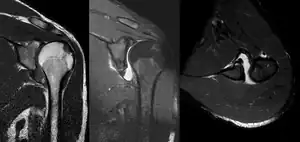

A diagnosis of shoulder dislocation is often suspected based on the person's history and physical examination. Radiographs are made to confirm the diagnosis. Most dislocations are apparent on radiographs showing incongruence of the glenohumeral joint. Posterior dislocations may be hard to detect on standard AP radiographs, but are more readily detected on other views. After reduction, radiographs are usually repeated to confirm successful reduction and to detect bone damage. After repeated shoulder dislocations, an MRI scan may be used to assess soft tissue damage. In regards to recurrent dislocations, the apprehension test (anterior instability) and sulcus sign (inferior instability) are useful methods for determining predisposition to future dislocation.